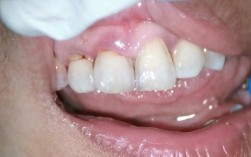

面部软组织改变:过度内收导致“瘪嘴”

牙齿是面部轮廓的支撑之一,前牙(尤其是门牙)对唇部有支撑作用,过度拔牙并内收前牙,可能使唇部失去支撑,出现“瘪嘴”、鼻唇沟加深,显得苍老,尤其对于骨量本身不足、面部软组织较薄的患者,风险更高。

误区2:“拔牙后脸一定会变凹”

真相:面型凹陷与“拔牙数量”无直接关系,而与“牙齿内收程度”及“面部基础”相关,拔除4颗第一前磨牙后,若前牙内收3-4mm,对于面部饱满者可能改善突度;而对于面部本身较平者,过度内收(如>5mm)则可能凹陷,医生会通过头影测量预测内收量,避免此类问题。